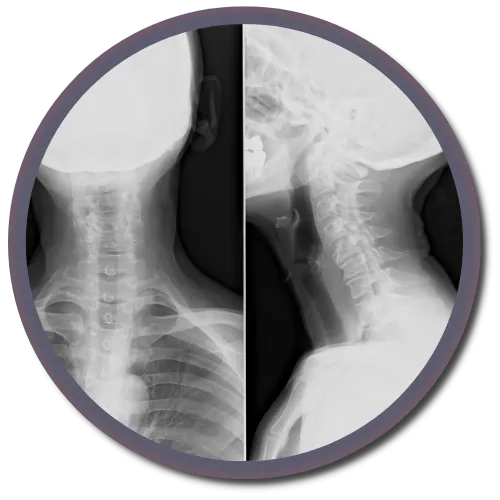

Pure Family Chiropractic uses the Gonstead method of adjusting and analyzing the spine. We're one of a few offices in Pellston that exclusively uses the Gonstead method. By thoroughly analyzing the spine through the use of x-ray, instrumentation, visualization, static and motion palpation you can expect a properly delivered adjustment.